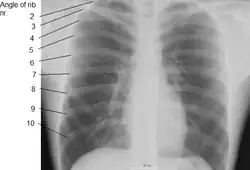

X-ray image of a human chest, with ribs labelled -